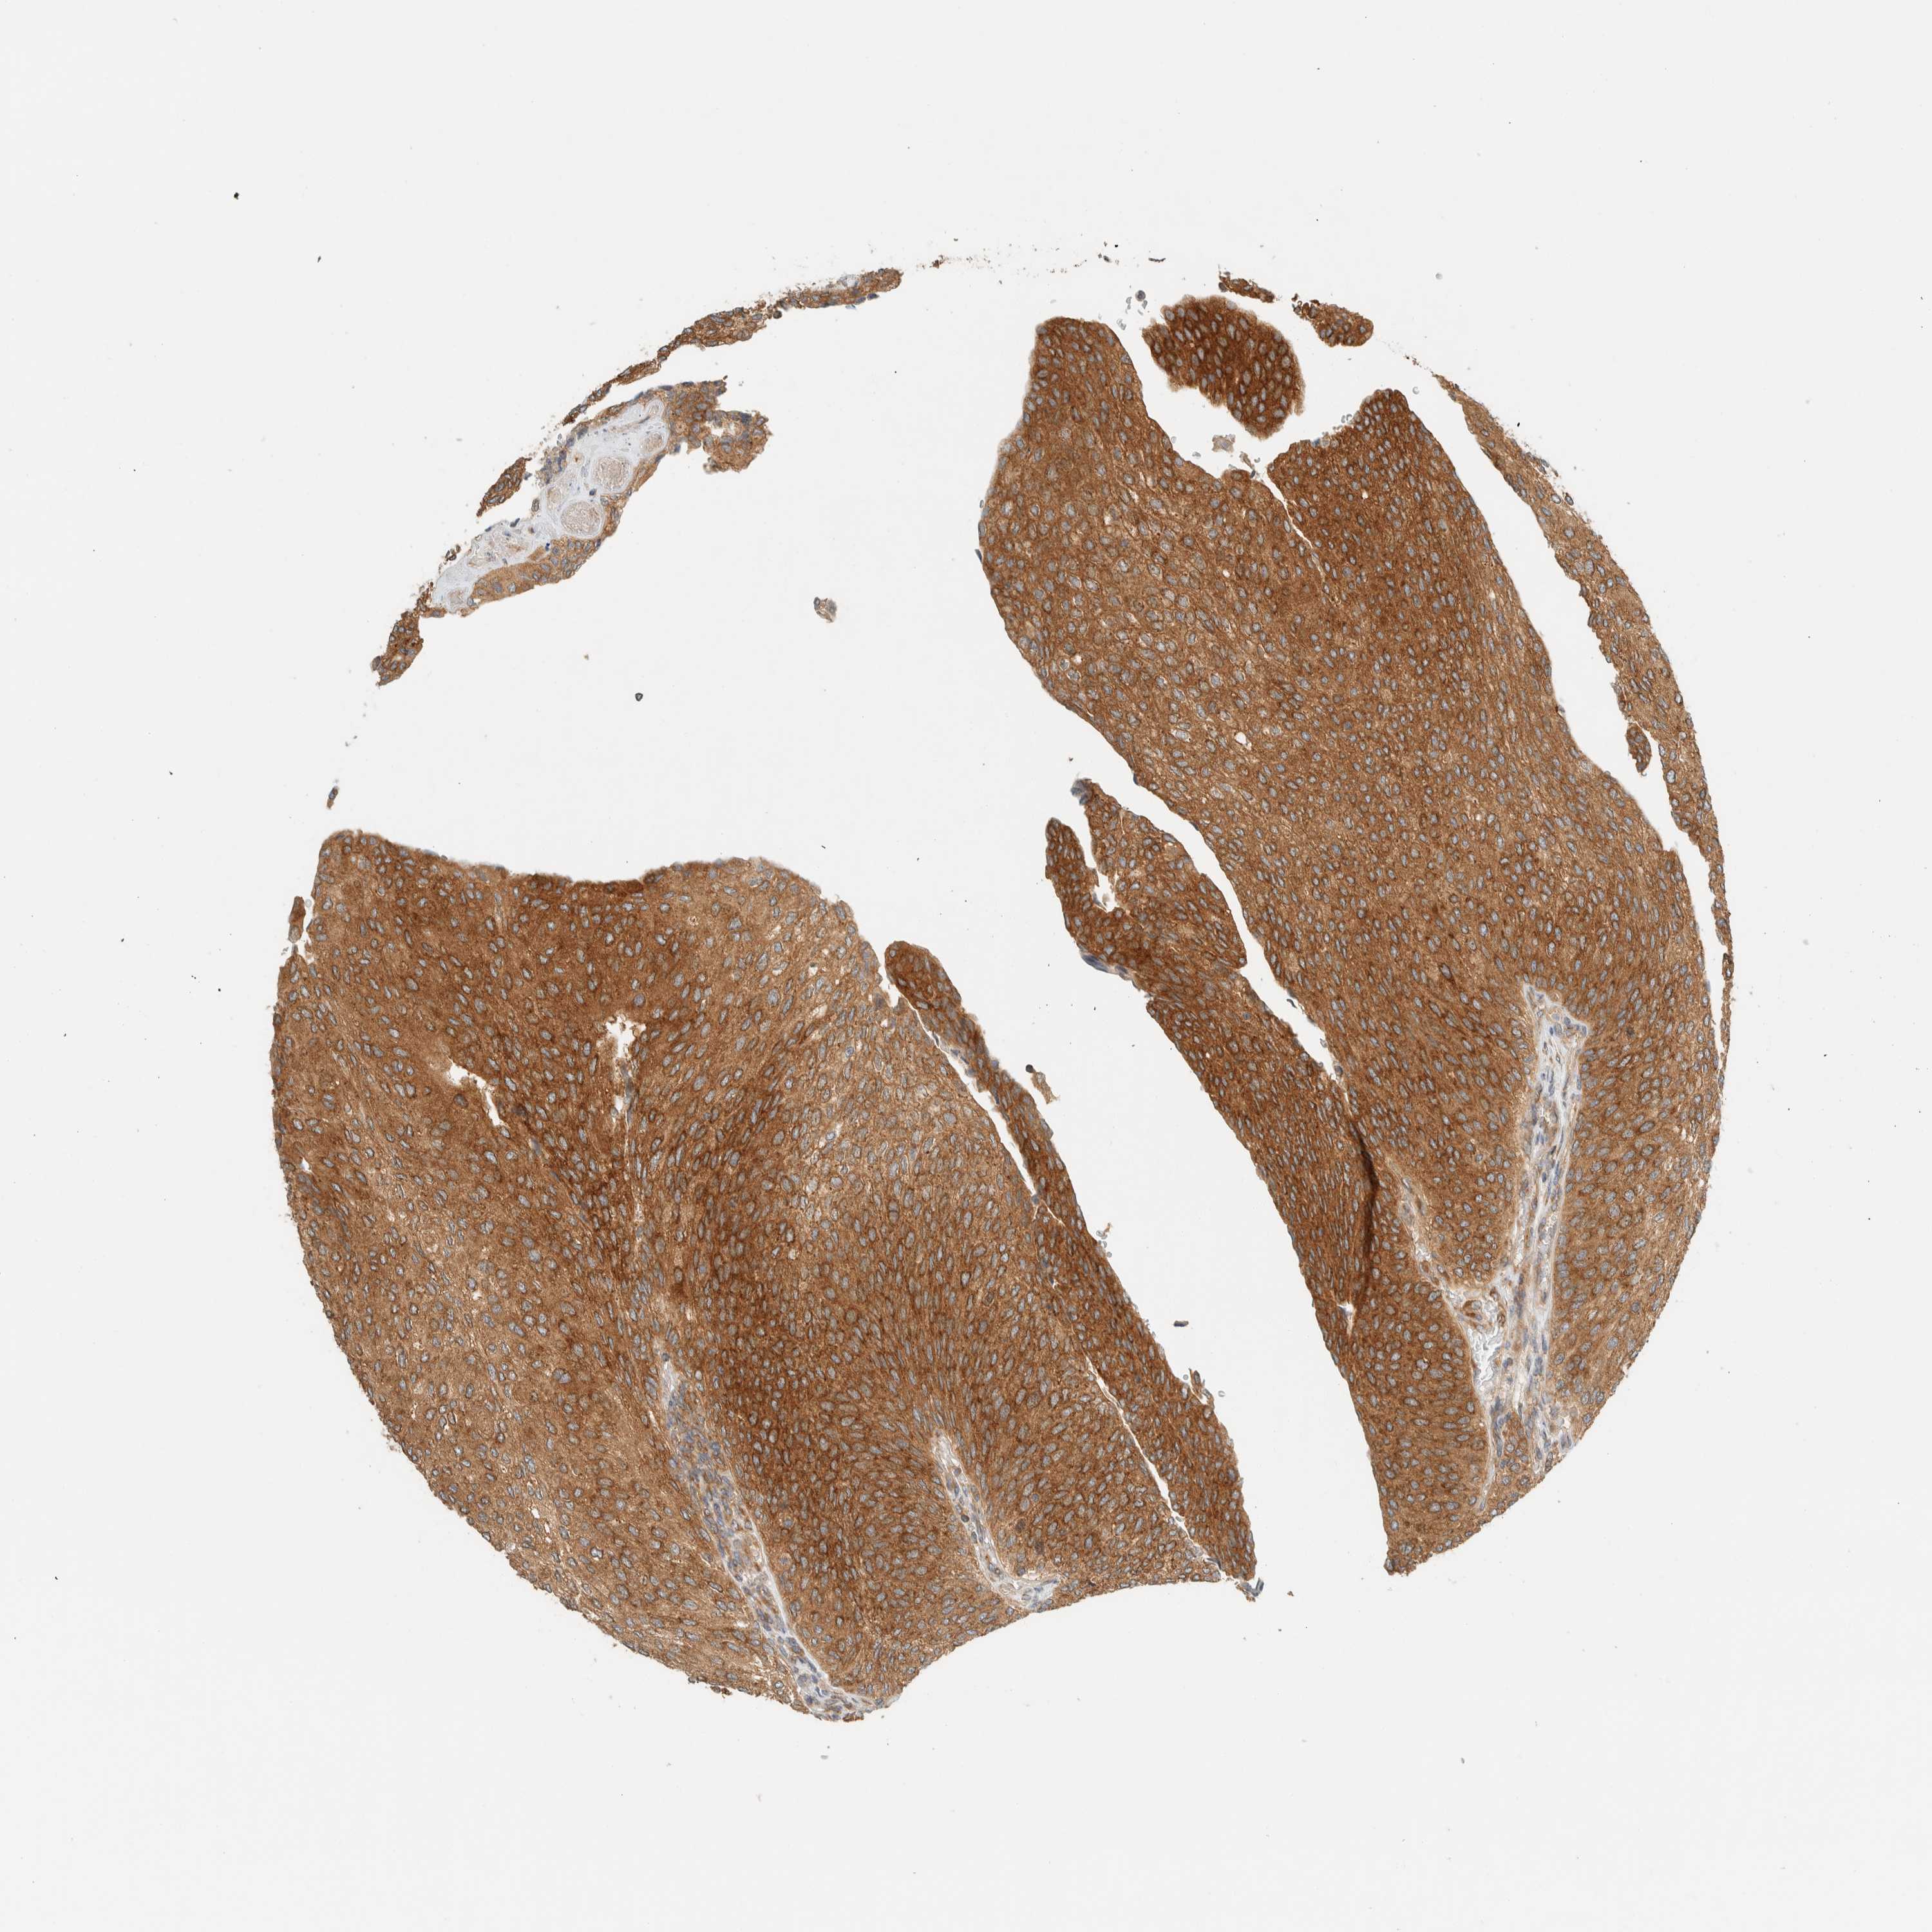

UROTHELIAL CANCER - Protein expressioni

A mouse-over function shows sample information and annotation data. Click on an image to view it in a full screen mode. Samples can be filtered based on level of antibody staining by selecting one or several of the following categories: high, medium, low and not detected. The assay and annotation is described here.

Note that samples used for immunohistochemistry by the Human Protein Atlas do not correspond to samples in the TCGA dataset.

Antibody stainingi

Antibody staining in the annotated cell types in the current human tissue is reported as not detected, low, medium, or high, based on conventional immunohistochemistry profiling in selected tissues. This score is based on the combination of the staining intensity and fraction of stained cells.

Each image is clickable and will lead to virtual microscopy that enables deeper exploration of all samples and also displays staining intensity scores, fraction scores and subcellular localization as well as patient and tissue information for each sample.

Antibody HPA023399

Antibody HPA023822

Urothelial carcinoma, Low grade

Urothelial carcinoma, High grade